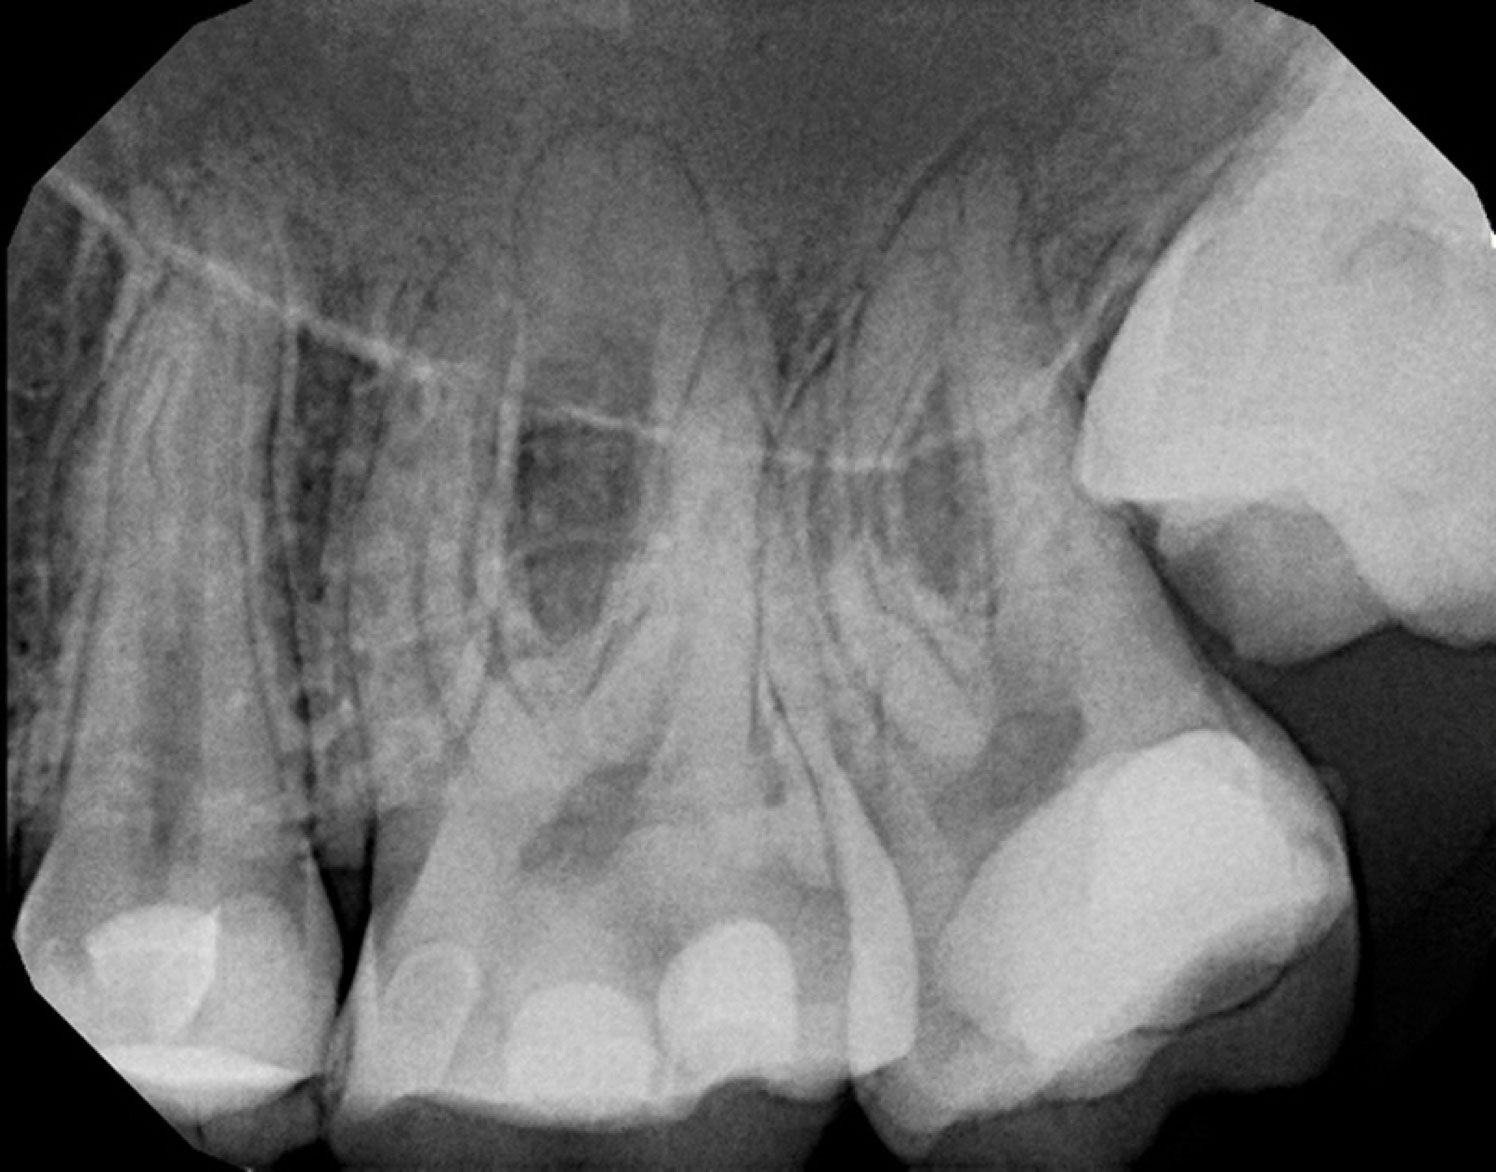

At our clinic, we use advanced imaging, microscope operating techniques, combined with our years of specialist training to diagnose and treat complex cases – all in a calm and supportive environment.

Our team of root canal specialists in Central London focuses on the identification and treatment of severe tooth pain. The types of procedures we do are usually highly complex and can include everything from emergency endodontic procedures to root end surgery or apicectomy. Thanks to our specialist team and state-of-the-art clinic, we can treat: